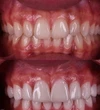

Zirkonyum uygulamalar

Porselen uygulamaları

Laminate veneer